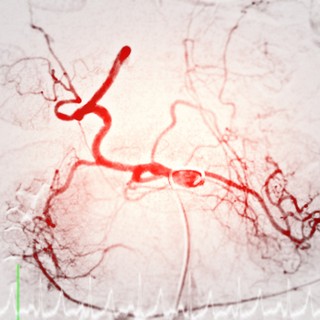

Az arteriográfia egy speciális orvosi képalkotó vizsgálat, amelyet az artériák állapotának felmérésére használnak. Ez a módszer kontrasztanyagos röntgenvizsgálaton alapul, és lehetővé teszi az érrendszer pontos megjelenítését. Az arteriográfiát gyakran alkalmazzák szív- és érrendszeri betegségek diagnosztizálására, érszűkületek vagy elzáródások kimutatására, valamint a stroke és a szívinfarktus kockázatának felmérésére.

- Kontrasztanyagot fecskendeznek be, amely az erekben áramolva kirajzolja az érrendszert a röntgenképeken.

- A röntgenfelvételek elkészítése során az orvos valós időben figyeli az erek állapotát.

- Az eredmények alapján megállapítható az érszűkület mértéke, az érfal rugalmassága és az esetleges szűkületek vagy elzáródások jelenléte.